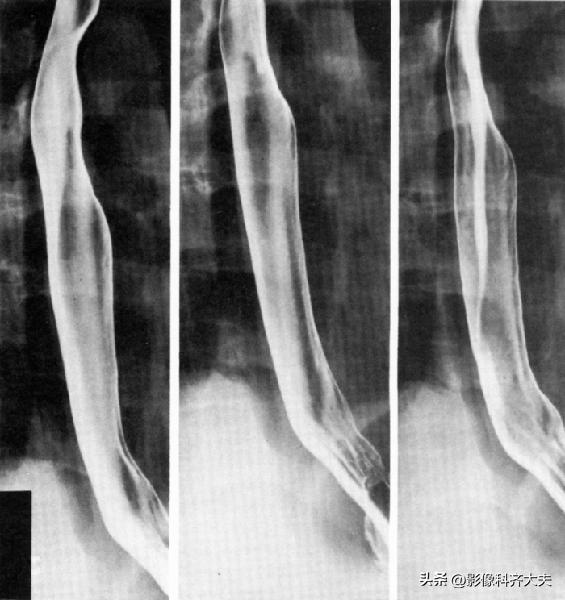

食管双对比相(站立右前斜位)

食管充盈相或粘膜相(站立右前斜位)